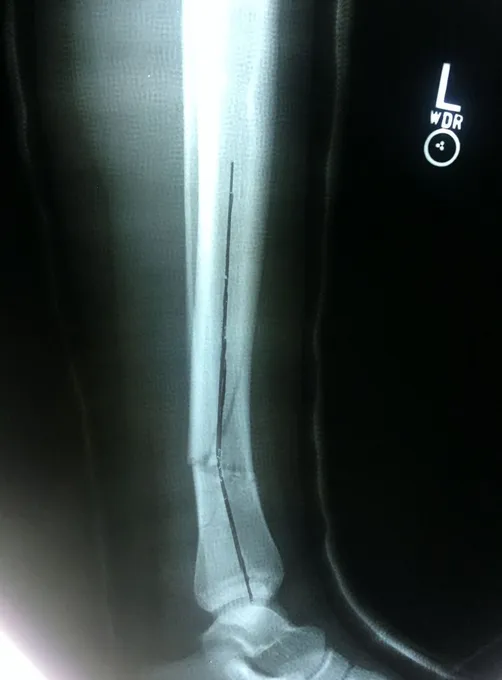

Displaced Tib-fib fracture that was treated with IM rod of the Tibia (below)